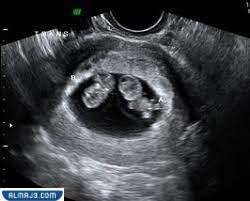

عندما يكون الطفل في الرحم، فإن يكون محاطًا بكيس أمينوسي (بالإنجليزية: Amniotic sac)؛ لتوفير الحماية له أثناء نموه، بالإضافة إلى امتلاكه لمشيمة، تعمل على توفير تدفق الدم، والمواد المغذية، أثناء الحمل، والأمر ذاته في معظم حالات حمل التوائم، إلا أن بعض حالات التوأم المتطابق، تشترك في كيس أمينوسي واحد، ومشيمة واحدة، وهو ما يعرف بالحمل بتوأم بكيس واحد[2]، كما يظهر في الجزء الأيمن في الصورة أسفله.

عادة ما يتم التعرف على الحمل بكيس واحد، من خلال صورة الموجات فوق الصوتية (بالإنجليزية: Ultrasound)، ويحدث هذا في وقت مبكر من الحمل، ويمكن الحصول على أفضل صورة، للتعرف على هذا النوع من التوائم، من خلال إجراء الصورة، في أول 14 أسبوعًا من الحمل؛ وذلك لكون المشيمة، والكيس الأمينوسي أكثر وضوحًا في هذه الفترة، ويظهر في الصورة، مشيمة واحدة، تقوم بإيصال الدم لكلا الجنينين، كما ستظهر الصورة، وجود كلا الجنينين، في كيس أمينوسي واحد، مع عدم وجود خط فاصل بينهما.[5]